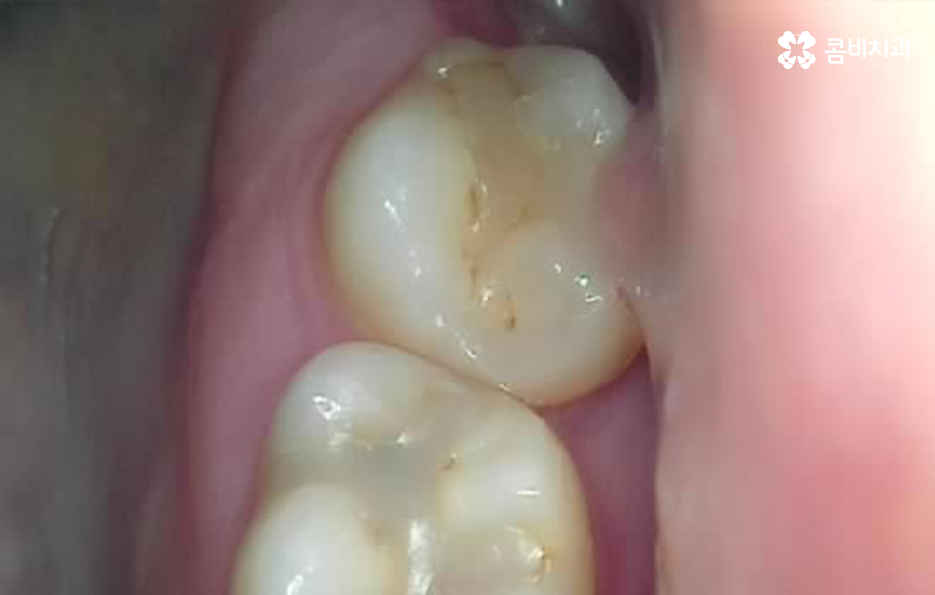

어금니는 주로 저작기능을 수행하고 있기 때문에 이물질이 사랑니와 어금니 사이에 껴서 발생되는 충치의 위험도 크지만 운이 좋게 충치가 발생하지 않았더라도 이물질이 사랑니와 어금니 사이에 치주질환을 일으켜서 조금씩 잇몸이 약하게 만들어서 잇몸 염증이 심해질 수 있으며 심한 경우 잇몸 뼈가 녹을 수가 있고 치아 뿌리 염증을 일으켜서 발치로 이어지는 사례도 있는데요